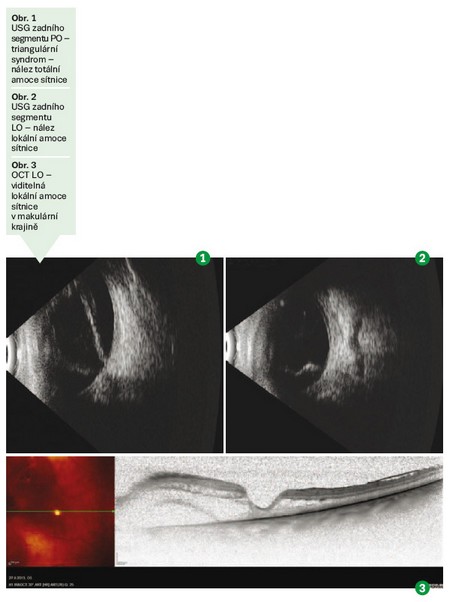

V únoru a březnu 2011 podstoupila pacientka operace v lokální anestezii FAKO + IOL na PO a LO v nemocnici v Ostravě. Následně jí byla v květnu 2013 z důvodu zastřeného vidění na obou očích provedena NdYAG kapsulotomie také v Ostravě. V červnu 2013 přichází na naši kliniku pro náhlé zhoršení zraku na PO. Byla jí diagnostikována amoce sítnice staršího data na PO. Následovala adekvátní vyšetření vzhledem k uvedené diagnóze. Byly provedeny VEP (vizual evokované potenciály) – nález na PO nevýbavný, na UZ Bscan popsán triangulární syndrom (totální amoce sítnice – obr. 1). Operace na PO nebyla doporučena – rizika byla větší než benefity. Při vyšetřeních byl zjištěn náhodný nález lokální amoce sítnice při VMTS (vitreomakulární trakční syndrom – obr. 2, 3). Pacientka je indikována k operaci PPV na LO.